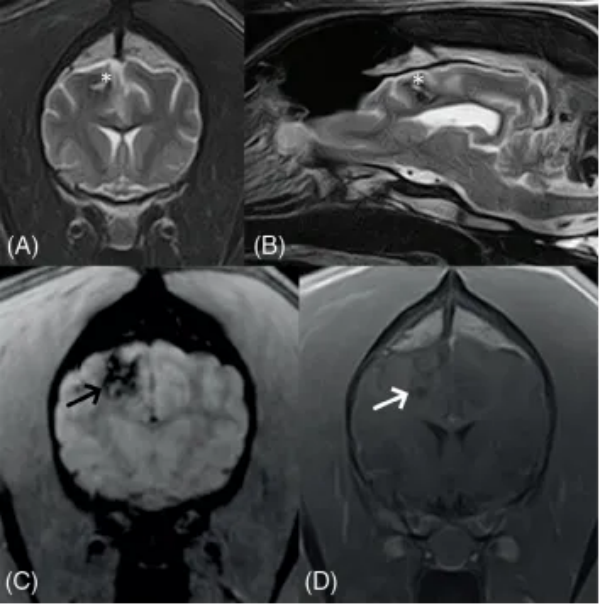

影像学、诊断与结果 在全身麻醉下使用1.5特斯拉磁共振成像系统对脑部和颈椎进行了MRI检查。获得的序列和成像平面包括:T2加权横断面图像、T2加权矢状面图像、T2加权液体衰减反转恢复背面图像、磁敏感加权成像横断面图像、扩散加权成像和表观扩散系数横断面图像、平扫及增强后T1加权横断面图像、T1加权背面图像。图像由一位委员会认证的兽医放射科医生和一位正在培训的兽医放射科医生使用软件以数字格式进行评估。 MRI显示右侧顶叶区域有一个边界清晰、卵圆形的轴内肿块,测量大小为(图1)。该病变对大脑镰产生显著的占位效应,导致中度向左的中线移位和双侧侧脑室的中度局部受压。该肿块在T2加权图像中与灰质呈等信号,依赖侧可见高信号的液-液平面,在T1加权序列和DWI序列中呈低信号,在ADC图中呈等信号。在T2加权以及SWI序列中,可见一薄而清晰的边缘低信号环勾勒出病灶轮廓。静脉注射钆对比剂后,肿块显示出微弱的边缘强化。周围白质在T2加权和FLAIR序列中显示出明显的、边界不清的高信号,在T1加权增强扫描中无强化。MRI结果与右侧顶叶急性轴内出血伴病灶周围实质水肿一致。T1加权低信号和T2加权等信号的表现以及病灶周围水肿支持急性病变。未发现其他脑部病变。 图1初次就诊时不同序列的脑部MRI图像:A, T2加权横断面和 B, 矢状面,C, 磁敏感加权序列和 D, 对比注射后T1加权序列(图片左侧为患者右侧)。在右侧顶叶,可见一个边界清晰、轴内、圆形至卵圆形、T2加权等信号和T1加权低信号的病变(星号),伴有薄层周边对比增强(白色箭头)。注意磁敏感加权序列中的低回声边缘,T2加权序列中围绕病变的黑边(黑色箭头),以及T2加权高信号的液-液线。病变周围白质存在边界不清的T2加权高信号,符合病灶周围水肿(箭头)。病变对大脑镰和侧脑室显示出中度的占位效应。T2 W, T2加权; T1 W, T1加权。 为了进一步调查凝血障碍的根本原因并评估合并症,使用CT扫描仪对胸部和腹部进行了CT检查。使用OsiriX MD进行了肺窗重建。 所有肺叶均显示明显的、中度的非结构性间质至肺泡肺模式,并伴有周边加重(图2)。观察到广泛的轻度支气管壁增厚,伴有多灶性支气管周围袖套征。总之,混合性肺模式及其周边加重最符合血管圆线虫感染引起的寄生虫性肺炎。可能性较小的鉴别诊断包括肺微出血、其他物种(例如狐环体线虫)引起的寄生虫性肺炎、细菌性或慢性支气管炎以及间质性肺炎。 基于这些发现,进行了贝尔曼-韦策尔幼虫迁移试验,发现了少量血管圆线虫幼虫。随后,开始了治疗方案,包括两次滴剂应用吡虫啉 400 mg/莫西克丁 100 mg,间隔2周。值得注意的是,在第一次滴剂治疗后仅3天,神经系统症状就有显著改善。这些症状逐渐改善,并在初次就诊后6周完全消失。 图2初次就诊时使用肺窗的肺部计算机断层扫描图像,A, 横断面视图,和 B, 背 面视图(图片左侧为患者右侧)。注意所有肺叶中周边加重的间质(星号)和肺泡(白色箭头)浸润。可以观察到广泛的支气管增厚伴支气管周围袖套征(箭头)。 尽管临床症状完全消失,6周后在同一机构使用相同的采集参数进行了脑部MRI检查,以持续监测右侧颞叶病变。获得的序列和成像平面包括:T2加权横断面图像、T2加权矢状面图像、T2加权 FLAIR 背 面图像、T1加权横断面图像、平扫及增强后T1加权 背 面图像、DWI和ADC横断面图像、SWI横断面图像。图像由与6周前相同的专家使用相同的程序进行评估。与之前的MRI扫描一致,在右侧顶叶检测到一个边界不清、形状不规则的T2加权低信号病变,中心呈T2加权高信号(图3)。该病变在T1加权上呈低信号,SWI呈均匀的信号缺失。在DWI和ADC序列中呈低信号,测量大小为 1.1 cm × 0.6 cm × 0.6 cm。静脉注射钆对比剂后未观察到对比增强。邻近的脑实质未见异常。 图3初次就诊后6周不同序列的脑部MRI图像:A, T2加权横断面和 B, 矢状面,C, 磁敏感加权图像和 D, 对比注射后T1加权图像(图片左侧为患者右侧)。与初次就诊相比(见图1),右侧顶叶实质内病变尺寸显著减小。它显示出边界不清的T2加权低信号轮廓,中心为高信号(星号)。T1加权序列显示低信号病变,无对比增强(白色箭头)。在SWI序列中观察到明显的信号缺失(黑色箭头)。未再注意到病灶周围T2加权高信号。T2 W, T2加权; T1 W, T1加权; SWI, 磁敏感加权成像。 总之,该病变符合缓解期的慢性轴内出血,缺乏病灶周围水肿。随后的血液检查显示VWF无进一步异常,颊粘膜出血时间在正常参考范围内。截至稿件准备之时,该犬临床表现正常。 讨论